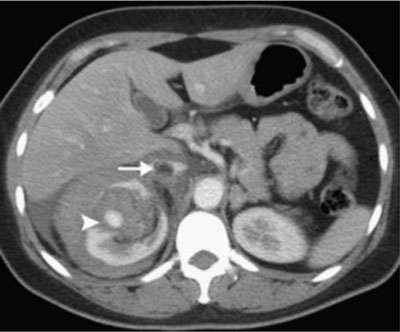

Figure 4

Contrast-enhanced CT showing two features: a perirenal hematoma and enhancing lesion with aneurysm formation (arrowhead) and a thrombus in the IVC (arrow) [15].